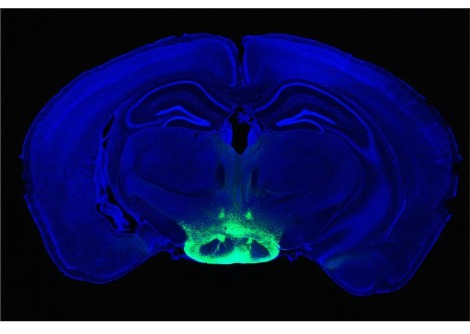

درس براون منذ فترة طويلة كيفية تأثر إيقاعات الدماغ عند البشر تحت التخدير العام عن طريق إجراء وتحليل قياسات الإيقاعات باستخدام أقطاب تخطيط كهربية الدماغ لفروة الرأس ، وإلى حد محدود ، الأقطاب القشرية في مرضى الصرع.  نظرًا لأن الدراسة الجديدة أجريت على نماذج حيوانية لتلك الديناميكيات ، فقد تمكن الفريق من زرع أقطاب كهربائية يمكنها قياس نشاط أو "ارتفاع" العديد من الخلايا العصبية الفردية والإيقاعات في القشرة والمهاد. قال براون إن النتائج تعمق بشكل كبير وتوسع نطاق النتائج التي توصل إليها في الناس.

على سبيل المثال ، نفس الخلايا العصبية التي قاموا بقياسها بالثرثرة مع ارتفاعات الجهد 7-10 مرات في الثانية أثناء اليقظة ، يتم إطلاقها بشكل روتيني مرة واحدة فقط في الثانية أو أقل أثناء فقدان الوعي الناجم عن البروبوفول ، وهو تباطؤ ملحوظ يسمى "حالة السقوط". إجمالاً ، أجرى العلماء قياسات متزامنة مفصلة للإيقاعات والارتفاعات في خمس مناطق: اثنتان في مقدمة القشرة ، واثنتان في الخلف ، والمهاد.